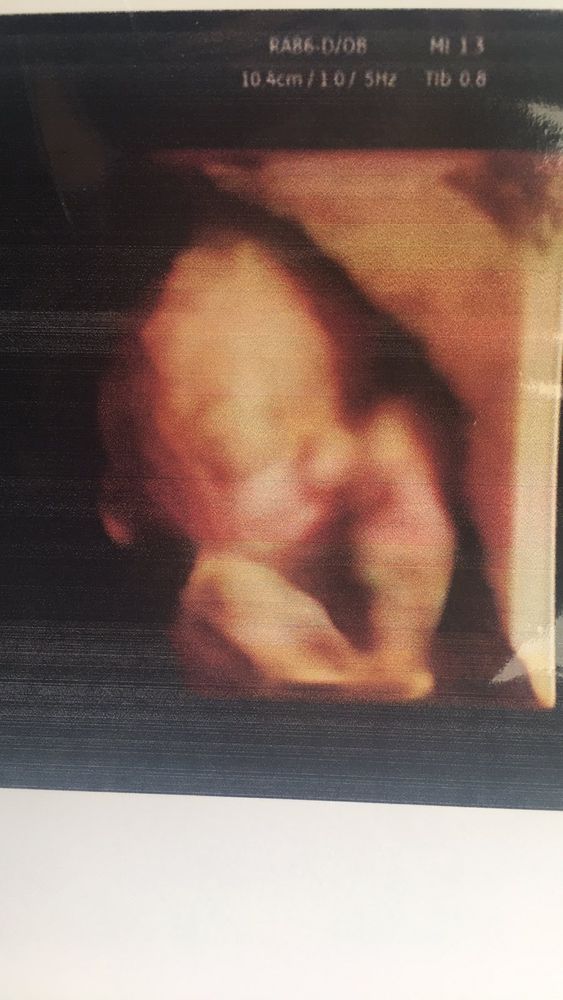

Результаты: УЗИ, КТГ, доплера, скринингаМоему мальчику уже 22 недельки) вес его 444грамма) очень активный и бьет маму постоянно )) днем и ночью ))) вот наша фотография сегодня)